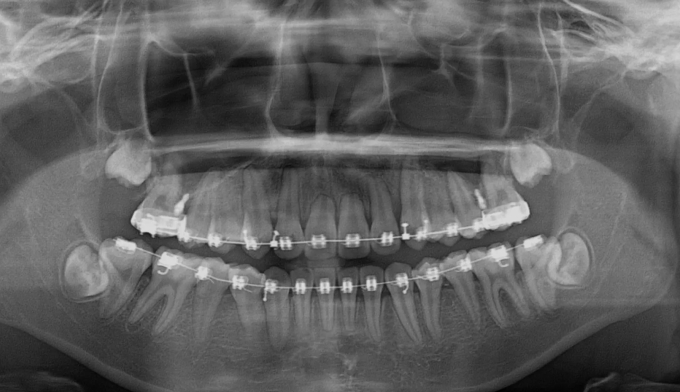

매복치의 방향이 수평으로 누워있기 때문에 저절로 구강내로 맹출하지는 못합니다.

따라서 잇몸 절개 후 교정장치를 부착하여 치아를 견인해주어야 합니다.

총 치료기간은 17개월 소요되었습니다.